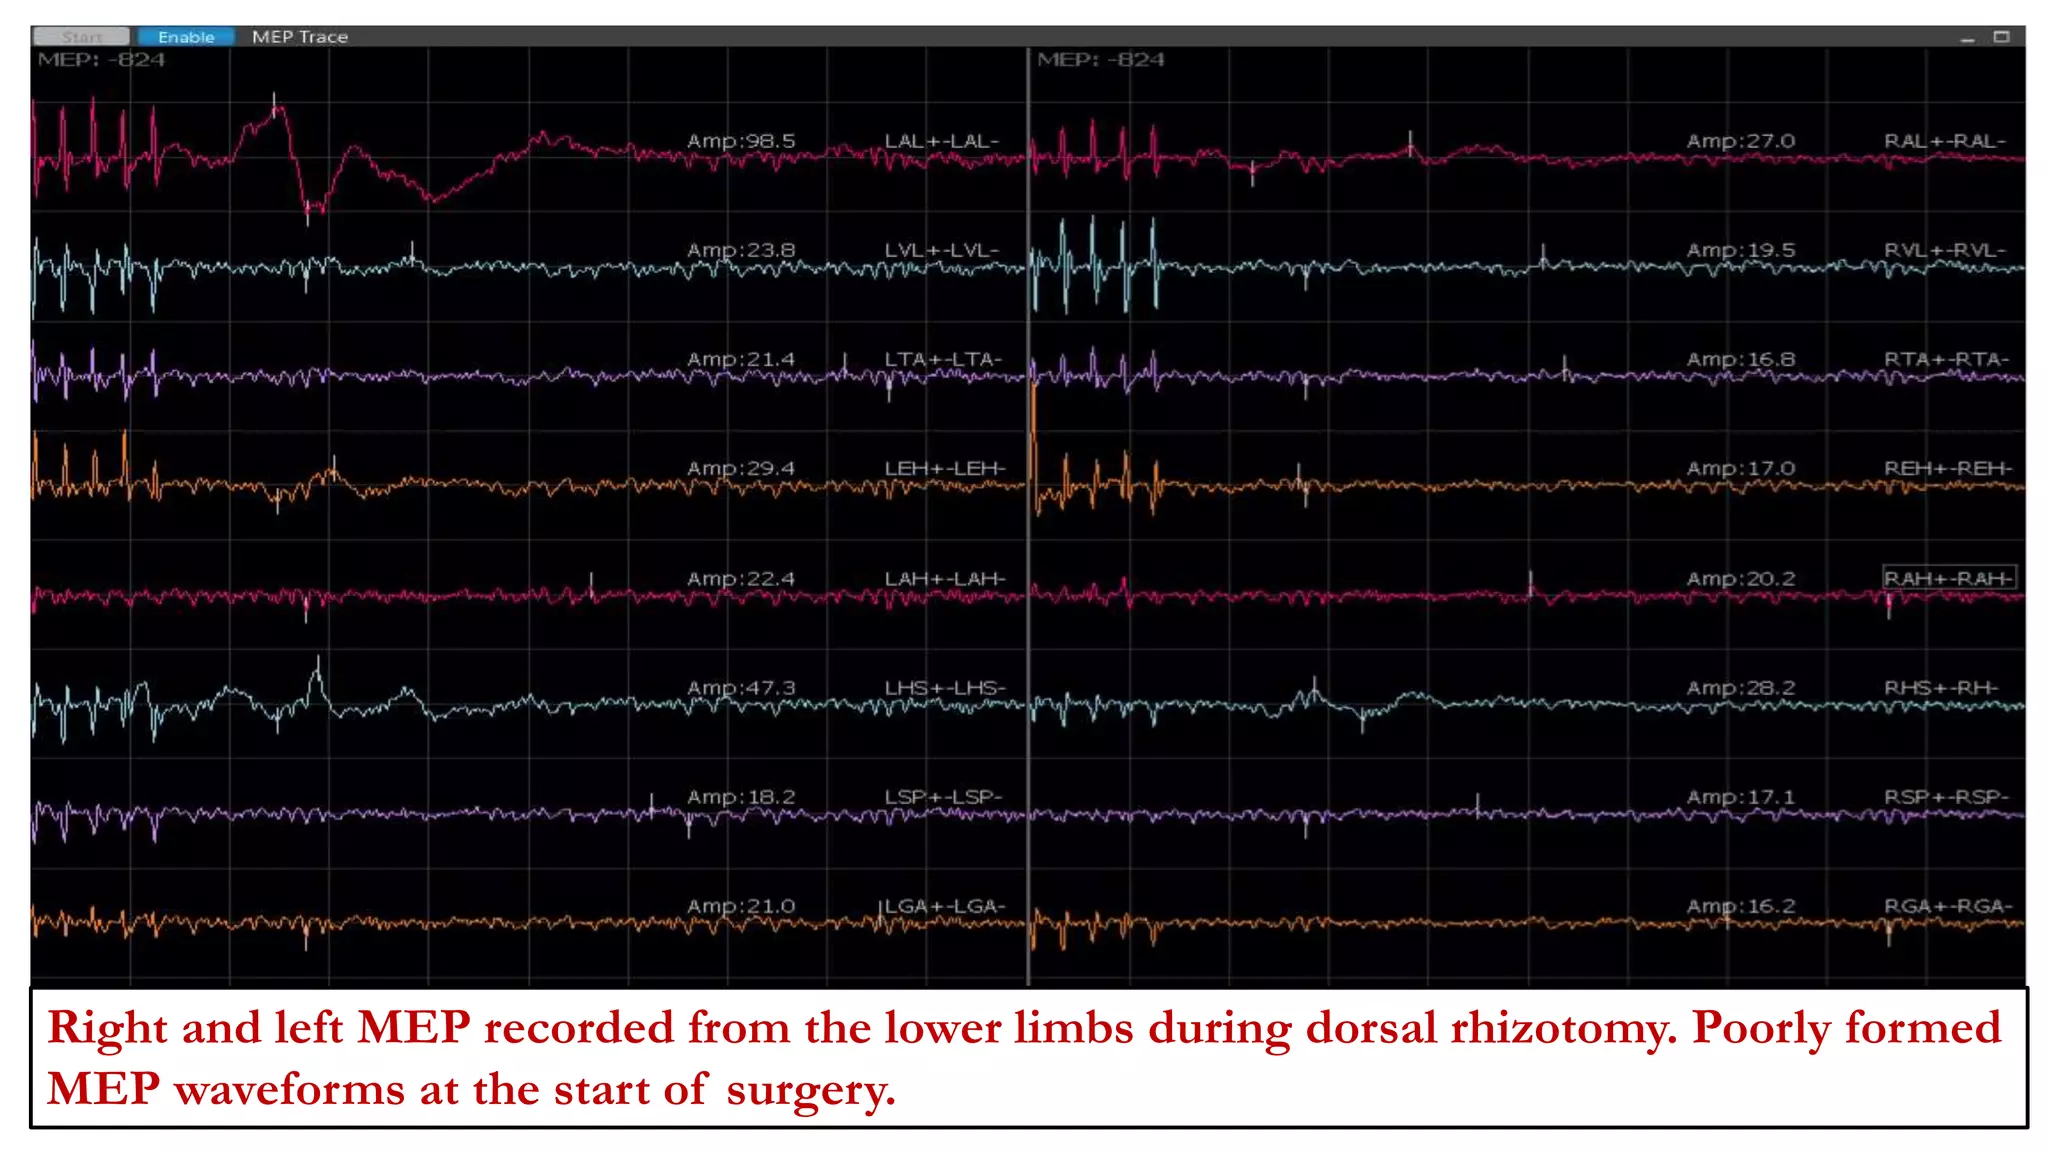

Right and left MEP recorded from the lower limbs during dorsal rhizotomy. Poorly formed

MEP waveforms at the start of surgery.